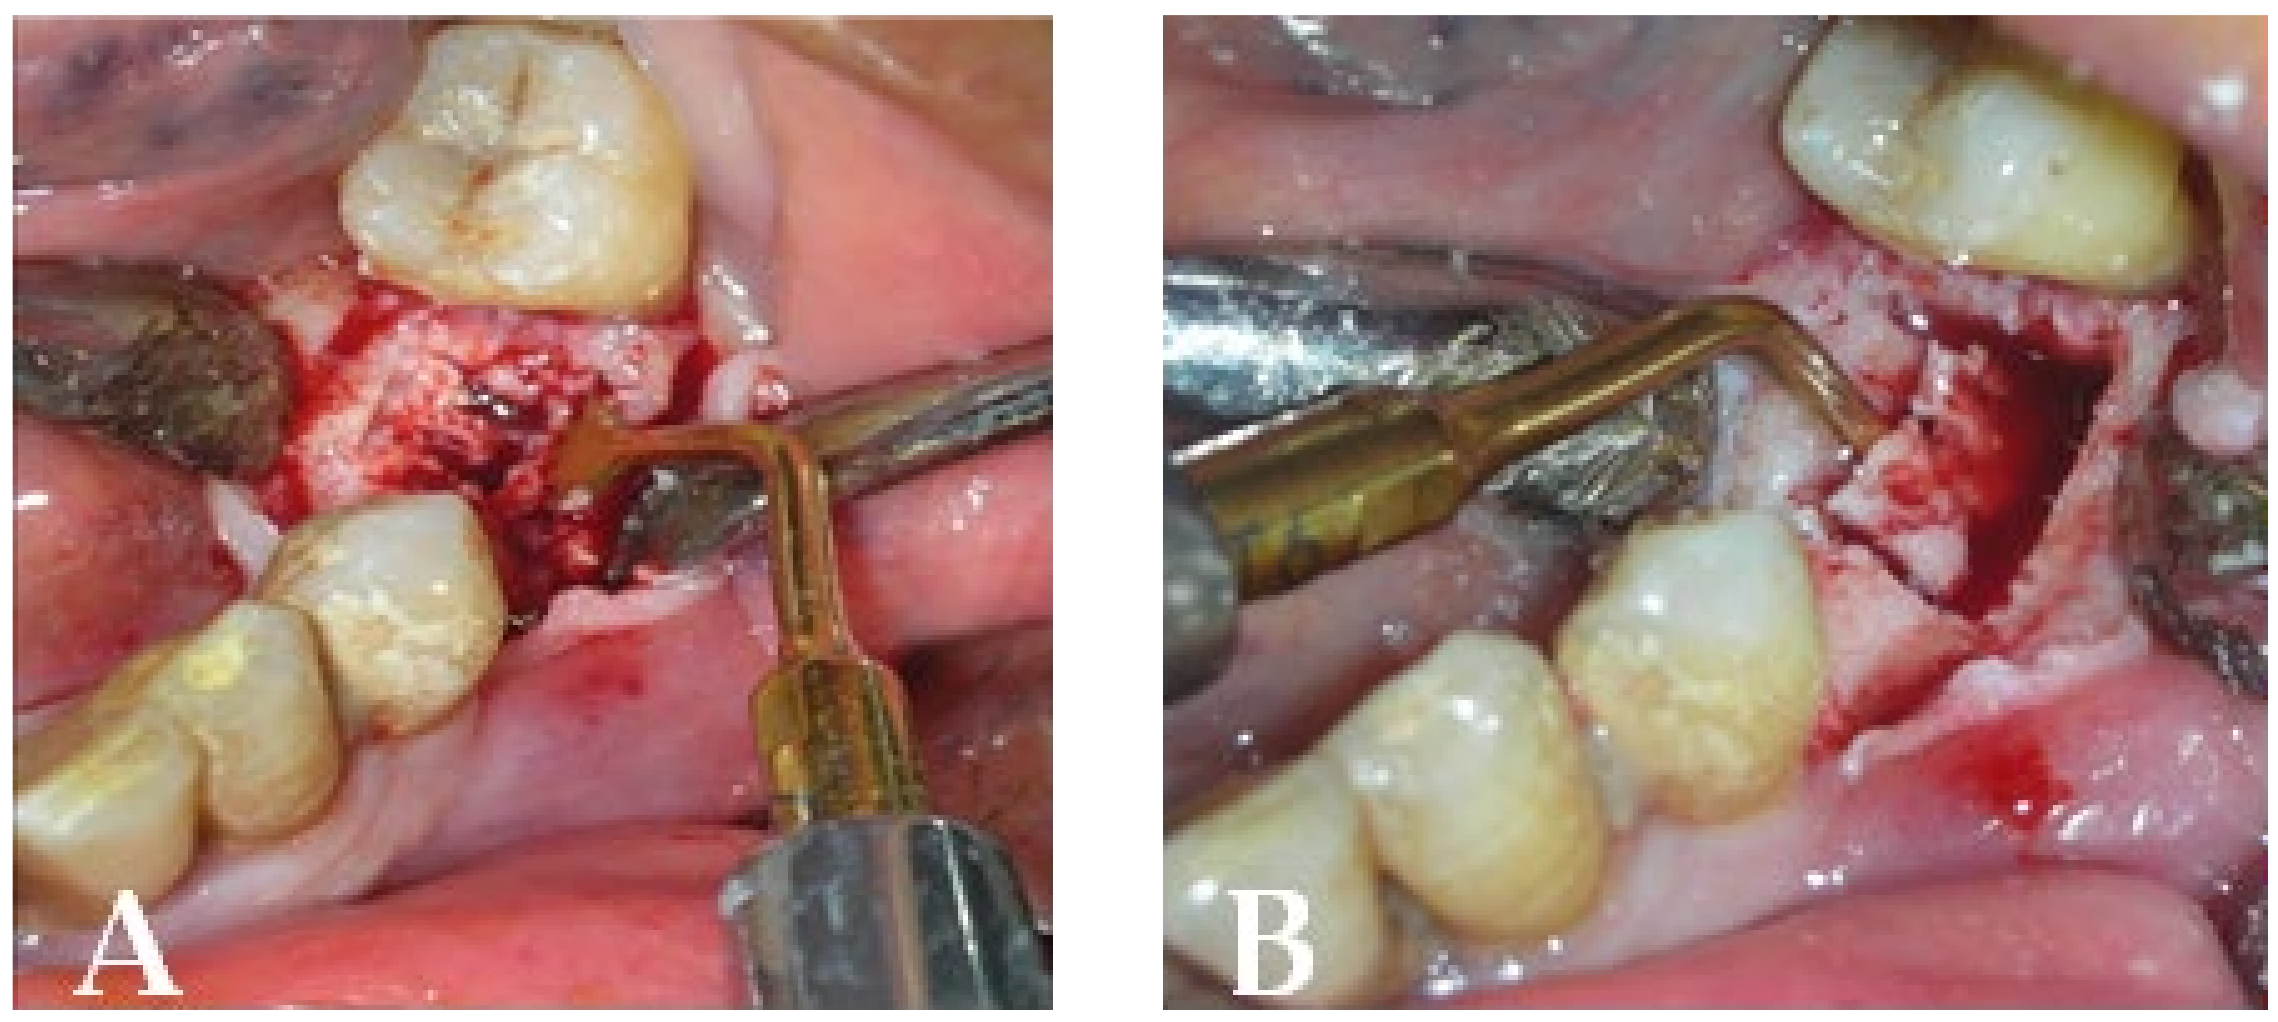

3.1. Clinical Case 1

3.2. Clinical Case 2